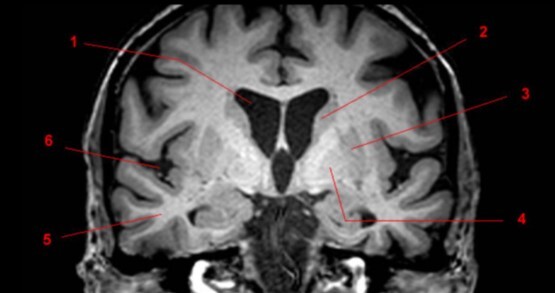

Label 3,5,7,10,11,12,14,20

3=Lt frontal lobe

5=Lt Lentiform nucleus

7=Lt internal capsule

10=Insula

11=Lt Claustrum

12=Rt Thalamus

14=Splenium, CC

20=Lt Interventricular foramen